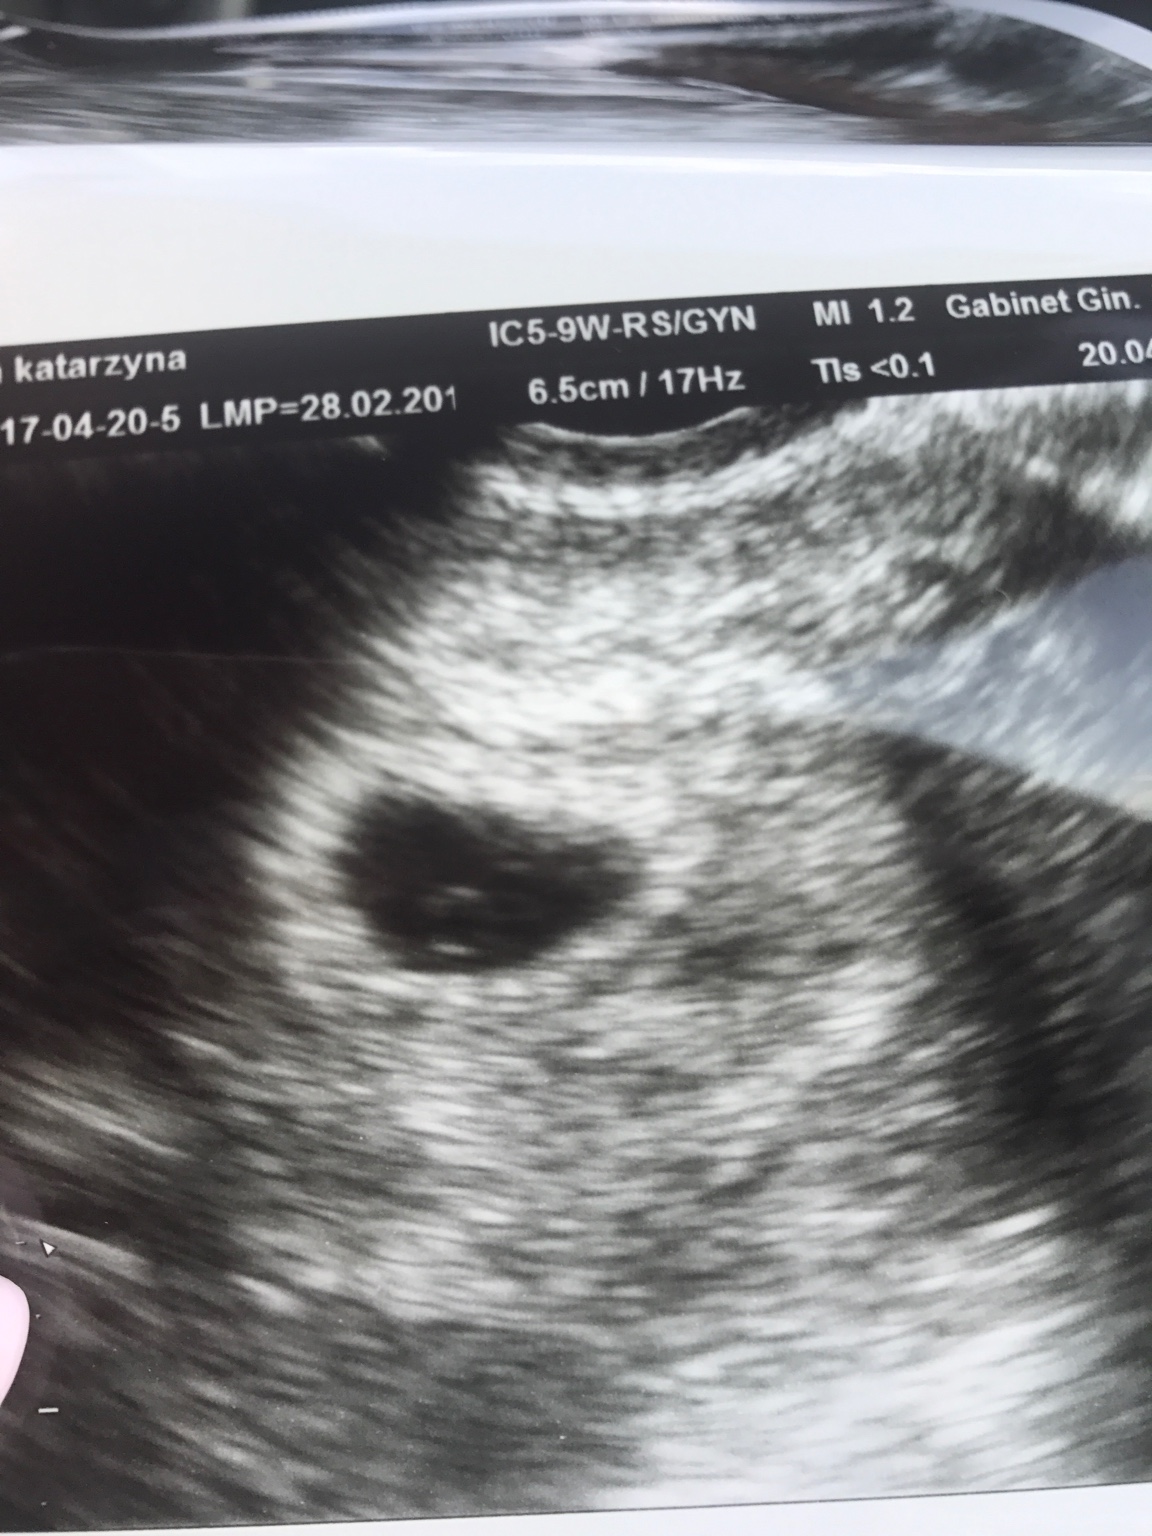

Bylam u gin w środę ale nic jeszcze nie widział. Kazał zrobić betę dwa razy co 48 h. Wczoraj robiłam i w sobotę jutro powtórka. Ale strasznie się zmartwilam, bo przez tydzien beta wzrosla tylko z 44 do 133

Niby, żeby był wiarygodny przyrost trzeba porównać z odstępem 48 h, ale to 44 i 133 to znacznie za mało.

Z tego co wyczytałam w necie to albo ciąża pozamaciczna albo puste jajo. Są laski, które piszą, że z takim niskim przyrostem bety ciąża rozwijała się prawidłowo, ale to pojedyncze przypadki.